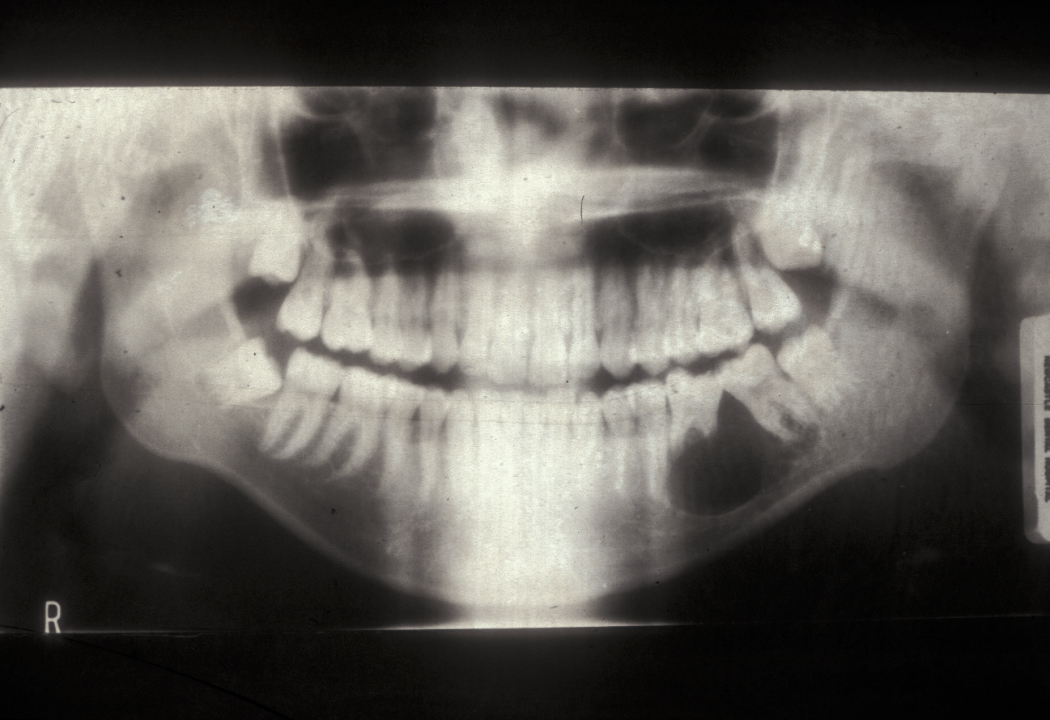

Imaging may be difficult because the radiographic findings lag behind the clinical stage. The first radiographic sign (see Figure 3) may be radiopacity which represents the sequestrum that has lost its non-mineralised components. Bone scans (PET scans) show osteomyelitis as areas of increased bone turnover (‘hot spots’).

Figure 3: Chronic osteomyelitis of the right mandible. Note the loss of the right condyle (part of the mandible forming the jaw joint) and the diffuse radiopacity of the right body of the mandible.